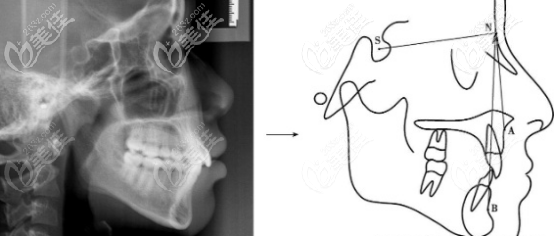

今天來(lái)回答“韓國(guó)雙顎手術(shù)和正頜手術(shù)有什么不同,和雙鄂手術(shù)適合哪些人做”兩個(gè)問(wèn)題。其實(shí)正頜手術(shù)和雙顎手術(shù)就是一個(gè)手術(shù),只是叫法不同罷了,國(guó)內(nèi)叫正頜,韓國(guó)叫雙顎,都是用來(lái)改善地包天。... b1700 G0 V0